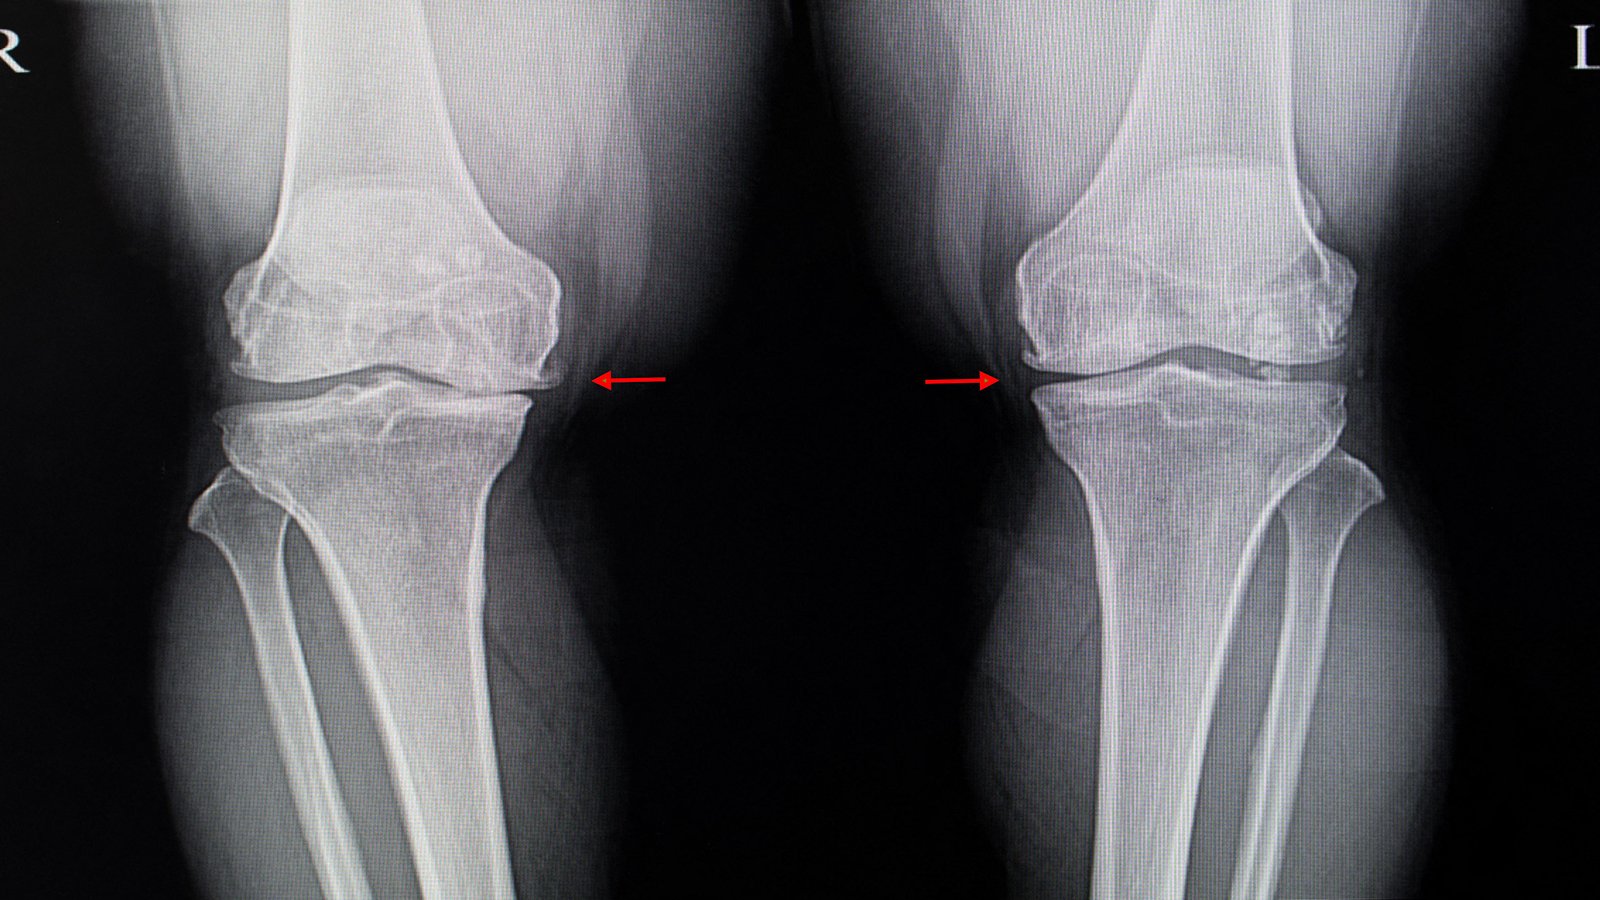

(MedPage Today) — Hopes that the plant extract known as diacerein could relieve pain and disability from osteoarthritis (OA) of the knee now seem forlorn in the wake of an Australian trial that failed to find any benefit.